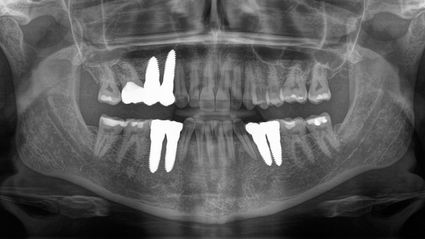

Ich wusste schon mein ganzes Leben lang, dass ich irgendwann Implantate brauchen würde, suchte aber nach einem Arzt, der meine Ziele mit der Optimierung meiner Gesundheit in Einklang bringen und einen individuelleren und "ganzkörperlichen" Ansatz bieten konnte. Auf einer Konferenz für funktionelle Medizin im Jahr 2016 lernte ich zufällig einen Arzt kennen, der mich an Dr. Volz verwies. Als ich im Oktober 2017 zum ersten Mal zu SWISS BIOHEALTH kam, hatte ich keine nennenswerten Gesundheitsprobleme, fühlte mich aber jeden Tag schrecklich müde, und obwohl ich meine Ernährung und meinen Lebensstil seit Jahren nicht verändert hatte, nahm ich langsam an Gewicht zu. Außerdem hatte ich ständig kalte Hände und Füße. Zusätzlich zu den 6 Implantaten, die ich benötigte, stellte Dr. Volz 4 Kavitationen fest und behandelte sie. Fast sofort hatte ich mehr Energie und war am Ende des Tages nicht mehr so müde.